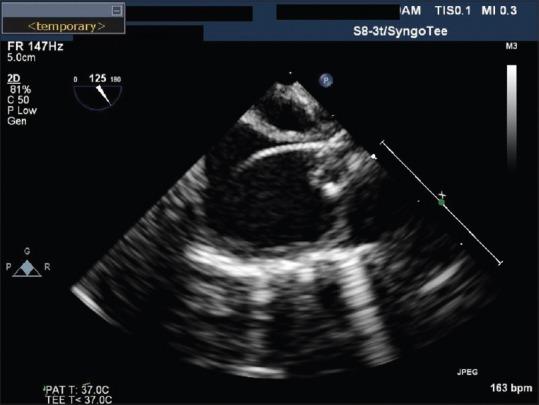

Retained intravascular foreign body is a well-known complication of central venous access placement in children as well as adults. Most of these foreign bodies are radio-opaque and hence are removed under fluoroscopy guidance. In our case, we describe the removal of an intracardiac radiolucent foreign body in an infant utilizing a combination technique - transesophageal echocardiogram and fluoroscopy.

血管内异物残留是儿童及成人中心静脉置管的一种常见并发症。这些异物大多是不透射线的,因此在荧光透视引导下取出。在我们的病例中,我们描述了采用经食管超声心动图和荧光透视联合技术为一名婴儿取出心内透射线异物的过程。